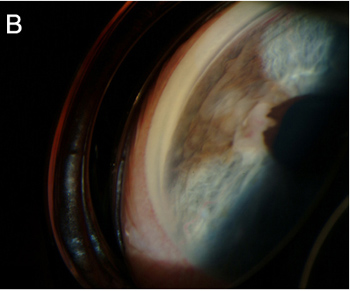

虹膜黑色素瘤病例

B)虹膜黑色素瘤前房角镜检查显示团块向外周虹膜扩展,但是没有侵入小梁网。